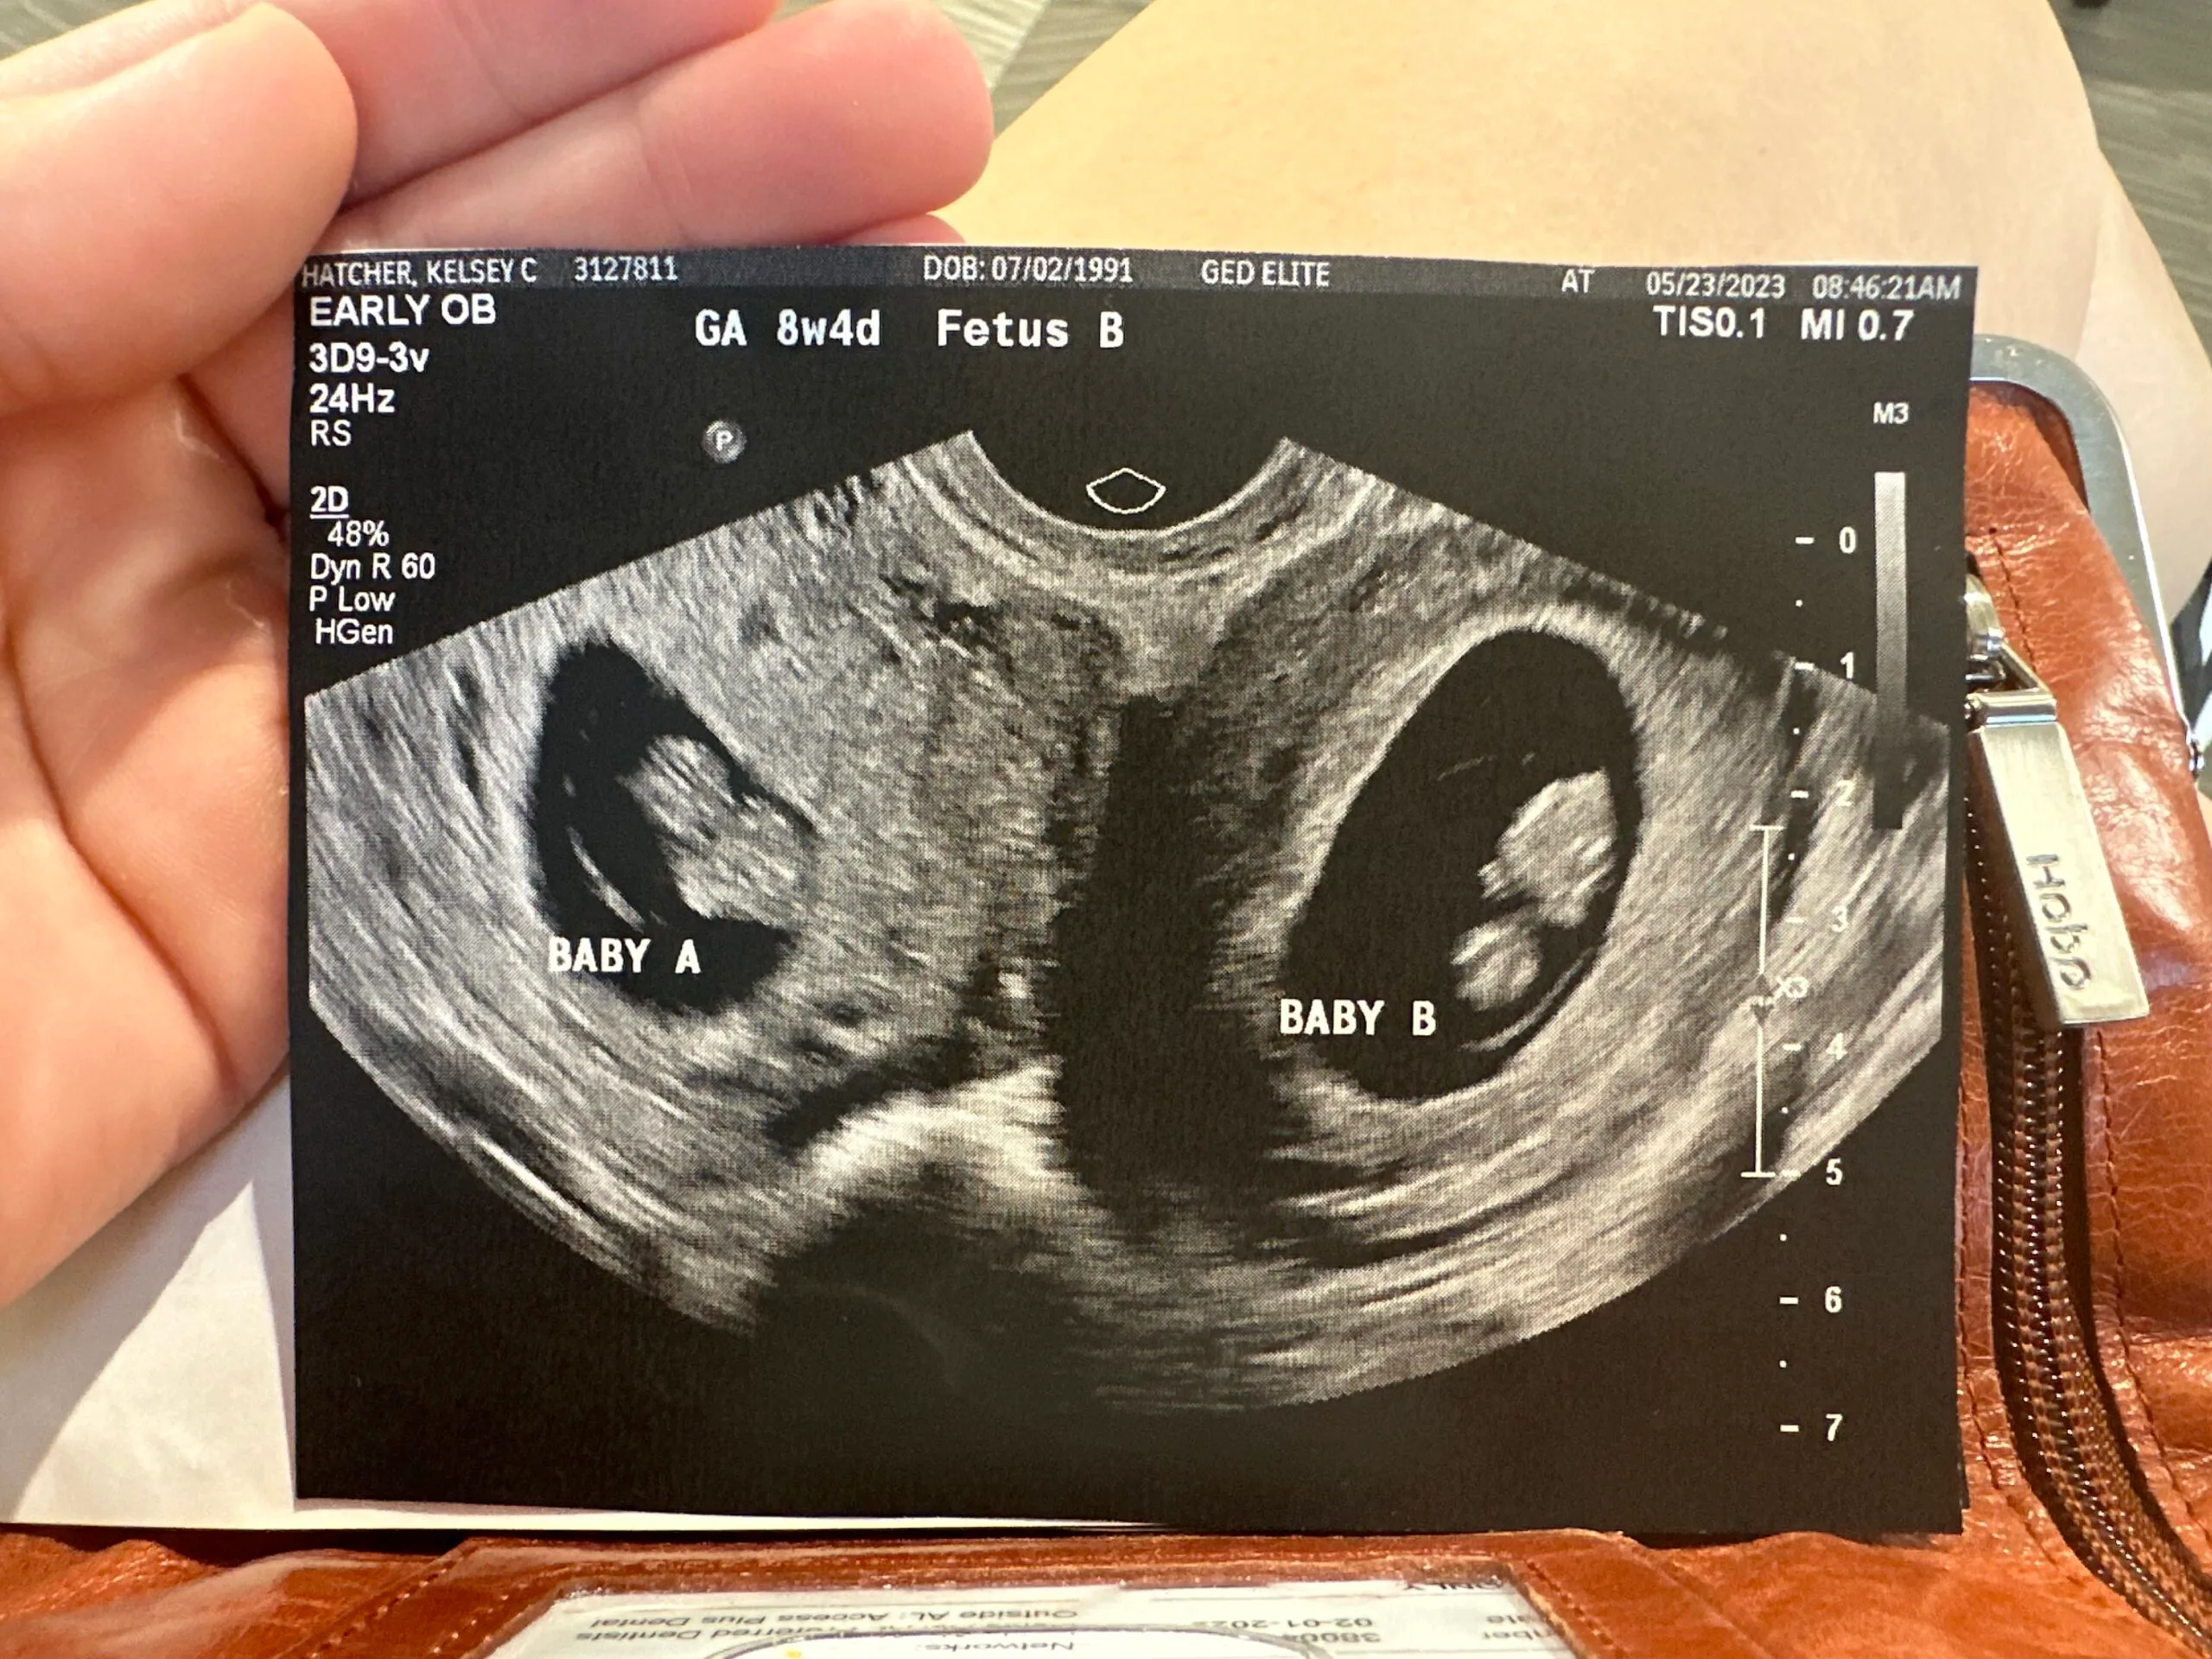

- In 2023, she fell pregnant again and discovered she was carrying twins — one baby in each uterus.

Eight weeks later at my ultrasound appointment, I couldn’t stop beaming as I marvelled at the little life on the screen.

‘Let’s hope there is just one,’ I joked to the sonographer, explaining my rare situation.

Anatomically I have one ovary attached to each of my wombs.

‘Well, no harm in checking,’ she replied, waving the wand over my belly again.

Then she paused.

‘Oh my gosh, there’s another one!’ she cried, showing me the second tiny bub.

I was so shocked, I burst out laughing. Picking up the phone, I called Caleb from the appointment.

‘It’s twins!’ I cried.

‘You’re kidding me,’ he replied.

‘Nope! One in each uterus!’ I added.

Amazingly, the babies measured the same exact gestational age, which means they were conceived at the same time!

I was shocked to learn the chances of falling pregnant with one baby in each uterus was about one in a million.